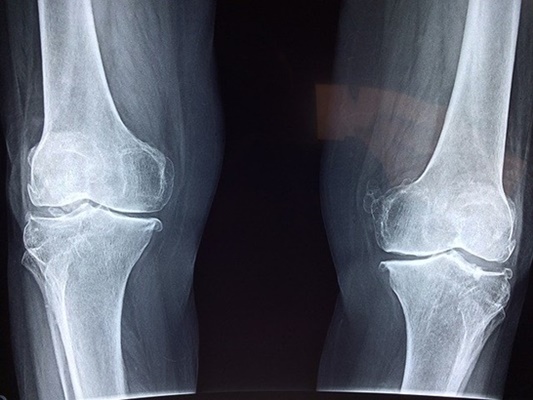

골밀도가 떨어지며 쉽게 골절을 당할 수 있기때문이고 미리 관리를 해두지 않으면 퇴행성 관절염 등과 같은 관절 질환이 생기고 악회되어 걸을 때 어려움을 겪을 수도 있습니다.

이러한 골정상은 골밀도와 연관이 있는데, 골밀도가 약하게 되면 뼈가 쉽게 손상되게 됩니다. 그리고 이러한 골절상은 뼈 건강이 좋지 못할수록 회복 속도도 더디고 심한 경우에는 회복을 하지 못할 수도 있습니다. 그렇기때문에 평상시 꾸준한 운동과 뼈에 좋음 음식들을 섭취해서 뼈 건강을 유지해야만 합니다.